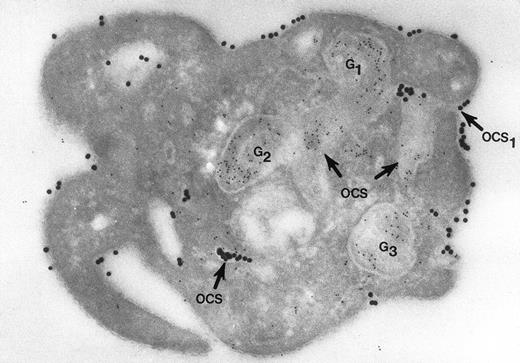

Nor would Morgenstern have made the comment that fusion of membranes of secretory organelles with membranes of the OCS has never been shown. The reports from our laboratory that he cited, and others,18 answer this concern quite well. In one of the experiments, platelets in suspension were combined with 20-nm colloidal gold particles coated with fibrinogen (Fgn/Au), then exposed to thrombin for 1, 3, and 5 minutes without stirring.19 At these intervals the platelets were fixed, frozen, and frozen thin sections prepared. The sections were stained with a polyclonal antifibrinogen antibody and then staph protein A bound to 10-nm gold particles. Thrombin stimulated uptake of 20 nm Fgn/Au gold particles into OCS channels and their transfer to α granules in the process of discharge into the OCS (Fig 1). Protein A 10-nm gold particles demonstrated fibrinogen in nonlabilized α granules and those in the process of discharge into the OCS. The work showed that the OCS was truly a final common pathway; hence, the name of the article.19

Cryosection of blood platelet from a washed cell suspension incubated with 18- to 20-nm colloidal gold particles coated with Fgn/Au for 5 minutes, then exposed to 1 U/mL of thrombin for 60 seconds. The Fgn/Au particles bind to the cell surface and penetrate into peripheral channels of the OCS. After fixation, freezing, and cryotomy, the frozen thin section was stained with a polyclonal antifibrinogen antibody and protein A bound to 5-nm gold particles. Immunogold beads detecting endogenous fibrinogen are concentrated in intact granules (G3) and in granules (G1, G2) in the process of discharging their contents into channels of the OCS. Some of the Fgn/Au particles entering from the outside are mixed with the immunogold beads in the same OCS channels (OCS) communicating with the exterior surface. Original magnification ×60,000. (Reprinted with permission.18)

Cryosection of blood platelet from a washed cell suspension incubated with 18- to 20-nm colloidal gold particles coated with Fgn/Au for 5 minutes, then exposed to 1 U/mL of thrombin for 60 seconds. The Fgn/Au particles bind to the cell surface and penetrate into peripheral channels of the OCS. After fixation, freezing, and cryotomy, the frozen thin section was stained with a polyclonal antifibrinogen antibody and protein A bound to 5-nm gold particles. Immunogold beads detecting endogenous fibrinogen are concentrated in intact granules (G3) and in granules (G1, G2) in the process of discharging their contents into channels of the OCS. Some of the Fgn/Au particles entering from the outside are mixed with the immunogold beads in the same OCS channels (OCS) communicating with the exterior surface. Original magnification ×60,000. (Reprinted with permission.18)